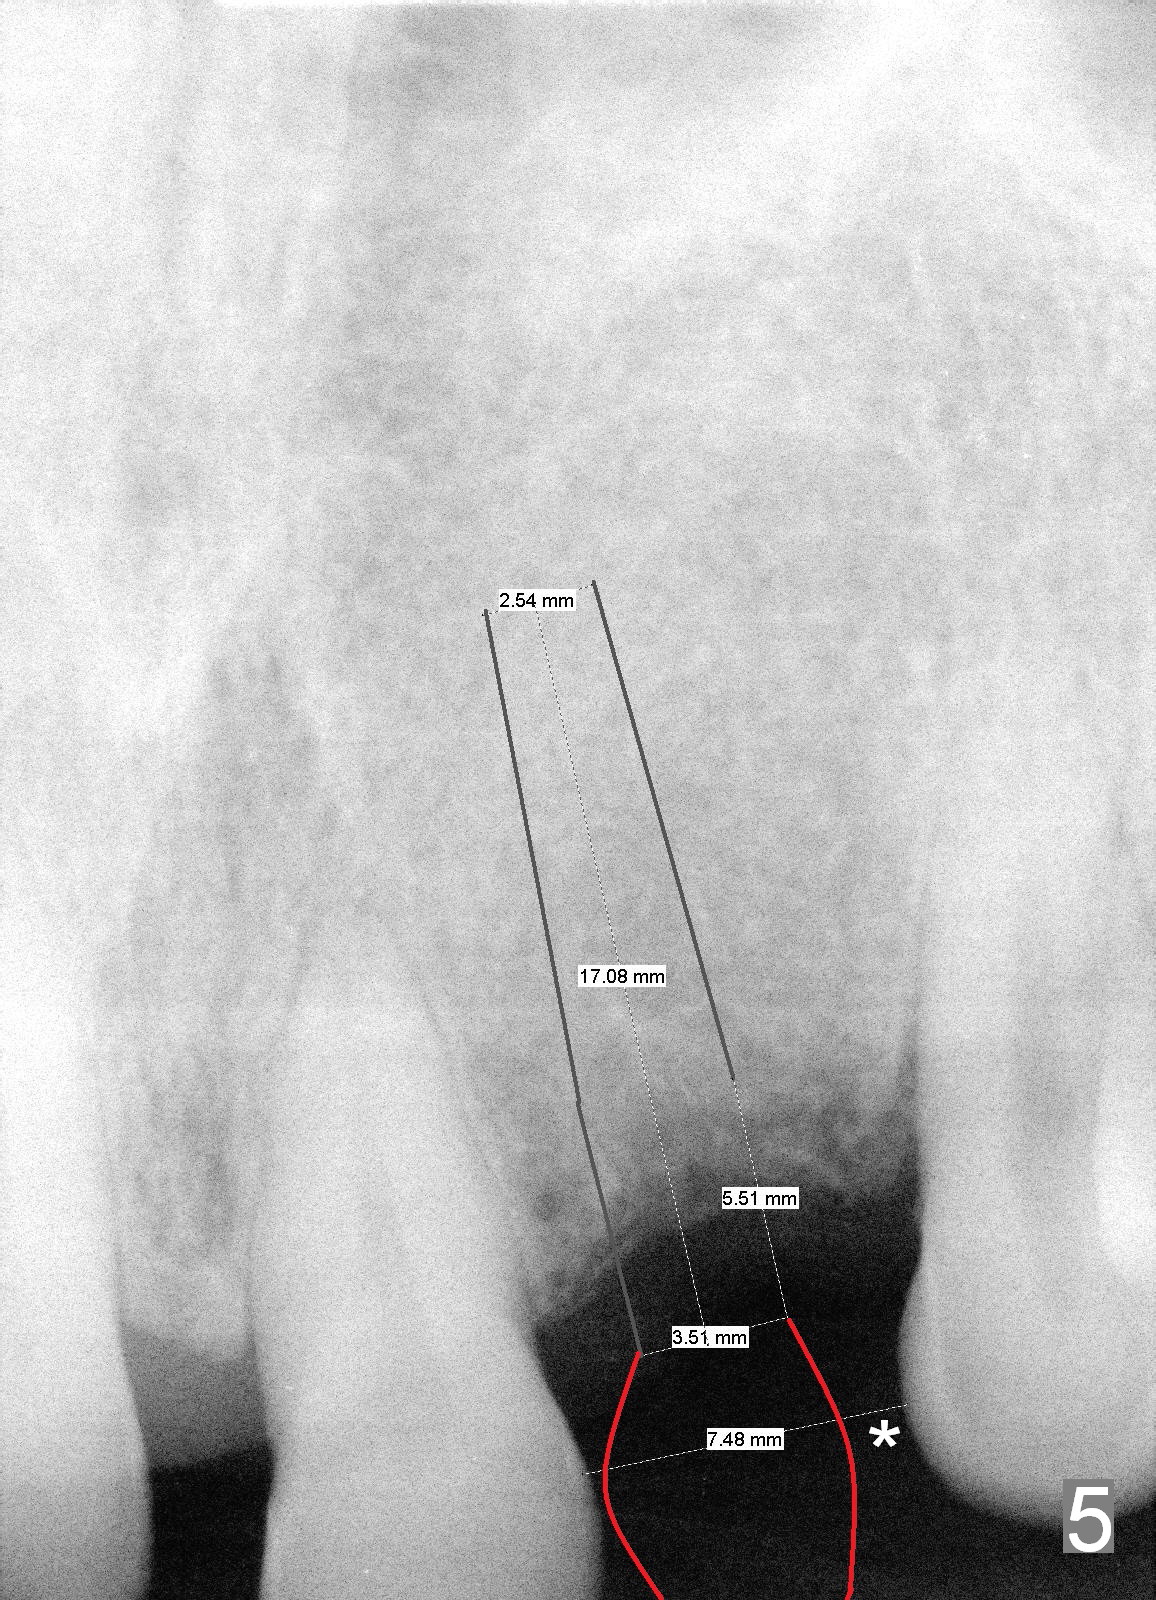

Although the edentulous space is not narrow at #10 (Fig.4), a small diameter implant should be used due to anterior diastemata (Fig.5). The implant will be placed slightly mesially to have a diastema distally (Fig.6 *). If there is a labial apical concavity, a shorter implant will be placed (14 mm). Also prepare angled 1-piece implants. Take preop photos to show the labial concavity if present.